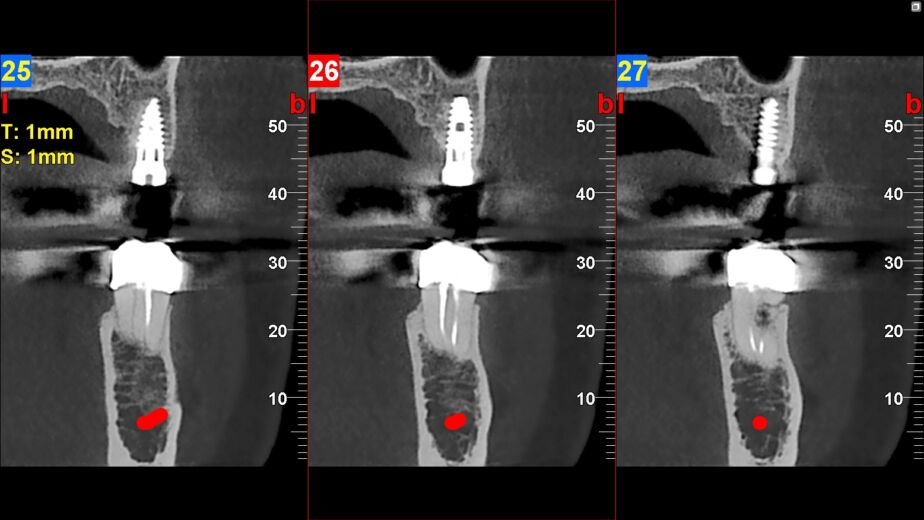

El estudio TAC macizofacial ofrece múltiples beneficios para la salud bucal, comenzando por su capacidad para detectar problemas en etapas tempranas. Gracias a su alta resolución y precisión, los dentistas pueden identificar caries ocultas, fracturas óseas o infecciones que no serían visibles en radiografías convencionales. Esto permite un diagnóstico más certero y un tratamiento más efectivo, lo que puede prevenir complicaciones futuras.

Otro beneficio significativo es su utilidad en la planificación de tratamientos complejos. Por ejemplo, en el caso de implantes dentales, el TAC proporciona información detallada sobre la densidad ósea y la ubicación de estructuras vitales como nervios y senos paranasales. Esta información es crucial para asegurar que el implante se coloque correctamente y minimizar riesgos durante el procedimiento.

El estudio TAC macizofacial se recomienda en diversas situaciones clínicas. Por ejemplo, es particularmente útil en casos donde hay sospecha de patologías como quistes o tumores en la región maxilofacial. También se utiliza en pacientes que requieren cirugía ortognática o implantes dentales, ya que proporciona información esencial sobre la anatomía del paciente.

Los resultados obtenidos a partir de un estudio TAC macizofacial son fundamentales para guiar el tratamiento dental adecuado. Las imágenes generadas permiten identificar anomalías estructurales como quistes, tumores o fracturas óseas con gran precisión. Además, se pueden evaluar condiciones como sinusitis maxilar o problemas relacionados con las articulaciones temporomandibulares (ATM), lo que ayuda a formular un diagnóstico integral.

Una vez analizados los resultados, el dentista puede discutir con el paciente las opciones de tratamiento más adecuadas basadas en los hallazgos del TAEsto no solo mejora la calidad del tratamiento recibido, sino que también proporciona al paciente una comprensión clara de su situación dental y las medidas necesarias para mejorar su salud bucal.

A partir de un estudio tac macizofacial se pueden obtener imágenes tridimensionales de la estructura ósea y dental, que permiten un diagnóstico preciso y la planificación de tratamientos dentales.